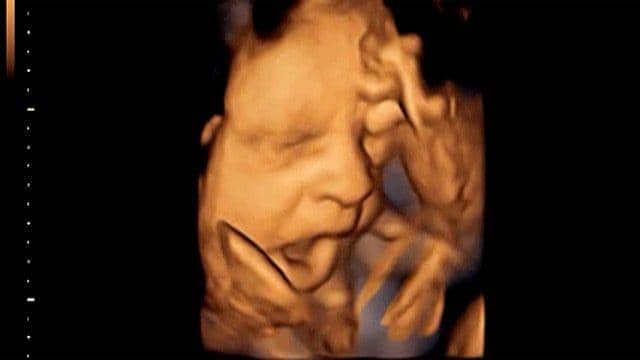

7. Bahkan, bayi di dalam kandungan pun bisa menguap!

Uniknya lagi, bayi di dalam kandungan bisa menguap, lho! Berdasarkan pencitraan di USG 4 dimensi, terlihat bahwa janin menguap berkali-kali di dalam rahim. Namun, ini bukan karena mengantuk atau bosan, ungkap laman BBC.

Menurut para ilmuwan, menguap pada janin penting untuk proses perkembangan otak. Janin akan sering menguap di awal kehamilan, tetapi akan mulai berkurang intensitasnya setelah 28 minggu di dalam kandungan.